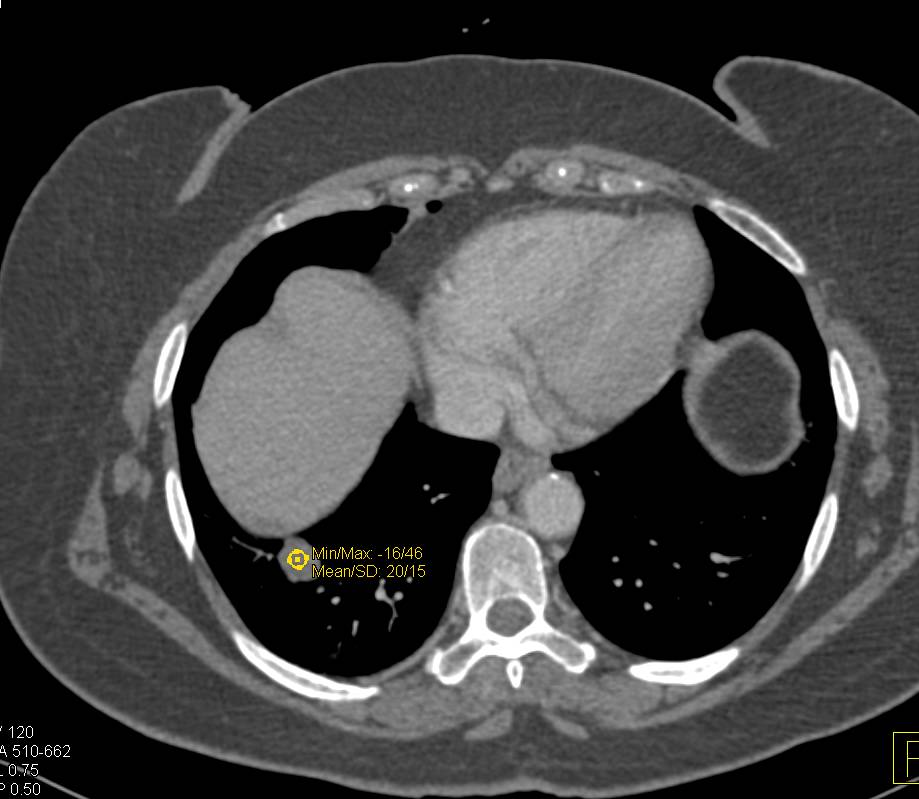

Ruptured Right Hemidiaphragm with Herniation of Bowel Above Liver